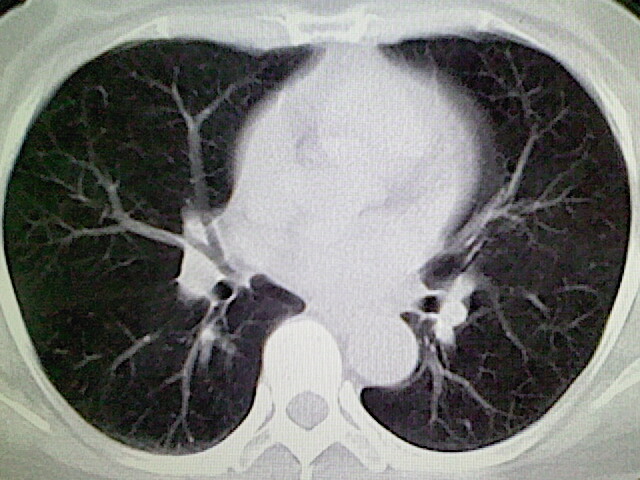

女,52岁,咳嗽,咳痰多日

左下肺陈旧纤维索条!

左肺舌段炎性改变

我见过几例,为炎症后纤维条索

慢性炎症后改变

考虑慢性炎性病灶粘连牵拉改变。

左肺舌叶纤维锁条病变。

左肺上叶下舌段炎症并局部胸膜反应。

左肺舌叶纤维索条影。

左肺舌叶段陈旧性病变

左肺舌段炎性反应。片子的质量太不好了。

左肺舌段炎性

炎性改变

左肺舌叶纤维索条影